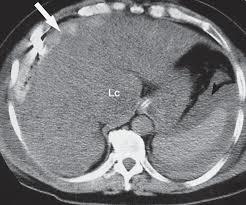

Qual o diagnóstico?

Colecistite aguda